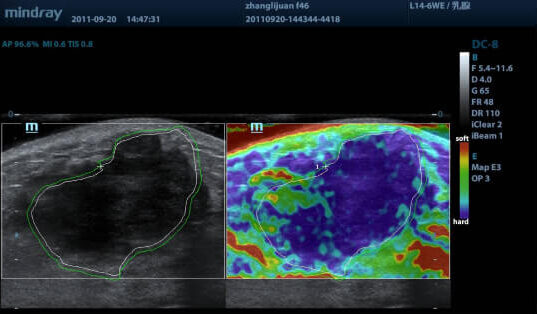

Эластография — технология УЗИ, которая позволяет проанализировать эластичность и плотность тканей. Здоровые ткани обычно упругие и мягкие, а патологические — жесткие.

unnamed-6-e1620510756862.jpg

Эта опция позволяет выявлять онкологию на ранних стадиях, узловые образования и другие патологии. Благодаря этому нет необходимости прибегать к биопсии.

STE — получение двухмерной цветовой эластограммы и количественной оценки эластичности.

• наличие наглядной цветной карты плотностей тканей;